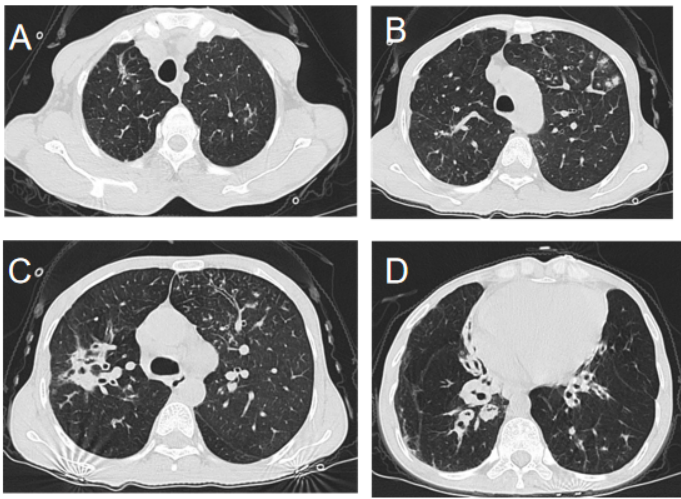

CT:双囊柱状扩片状条索增粗(图1)

图1  双肺支气管囊柱状扩张,周围少许斑片状影,支气管血管束增粗。双侧肺门及纵隔未见增大淋巴结。